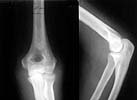

A female 48 years old sustained multiple injuries after fall from 5th floor 28/04/02. Among other injuries there was open posterior elbow dislocation (see attachment). It was reduced and the wound at the medial side of the joint debrided at the initial hospital. May 7 she was transferred to us. The wound healed primarily.

Yesterday (3 weeks post reduction) the plaster was removed to start motions. Gross elbow instability was revealed - the forearm easily can be displaced medially, and reduced back. Recent films with and without subluxation also attached.